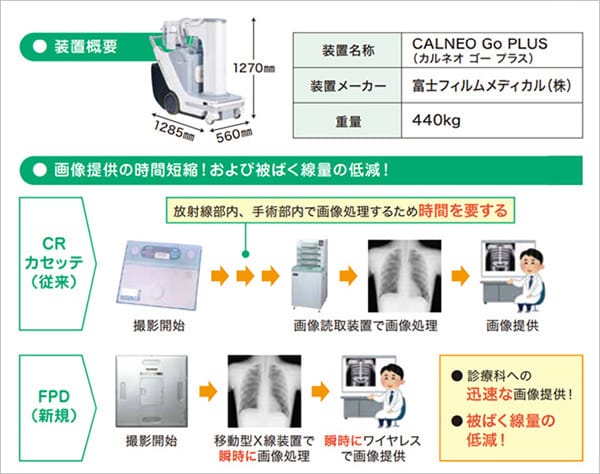

当院では、CALNEO Go Plus(2021年導入)装置2台が稼働しています。病室撮影は、放射線部内のX線撮影室での撮影が困難な場合に病棟などで、装置を患者さまのそばまで移動させてX線撮影を行います。従来、移動型X線装置はCR(コンピューテッド ラジオグラフィー)カセッテ内のIP(イメージングプレート)というものに記録した画像を画像読取装置で読み取り、画像化していました。今回、新たに導入された移動型X線撮影装置はCRカセッテではなくFPD(フラットパネルディテクタ)という方式を搭載しています。FPDはCRカセッテと違い、直接X線を読み取れるため撮影するとすぐに画像化ができ、高感度・高精細な画像をより少ないX線量で得ることができます。FPDはCR カセッテのように撮影毎に交換する必要もなく、繰り返し使用できるという特徴もあります。